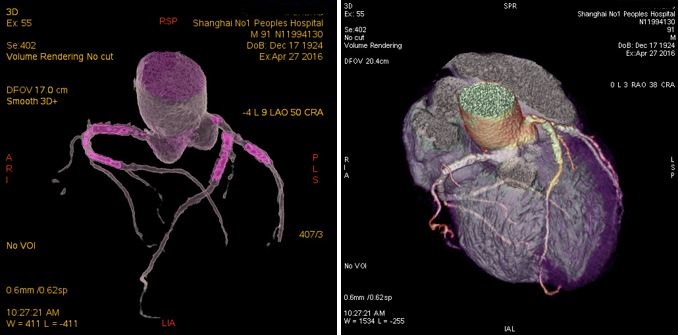

患者男性,91岁。PCI术后,心率57-233BPM,患者心律失常,因年老不能配合呼吸控制,Revolution冠脉检查采用自由呼吸。